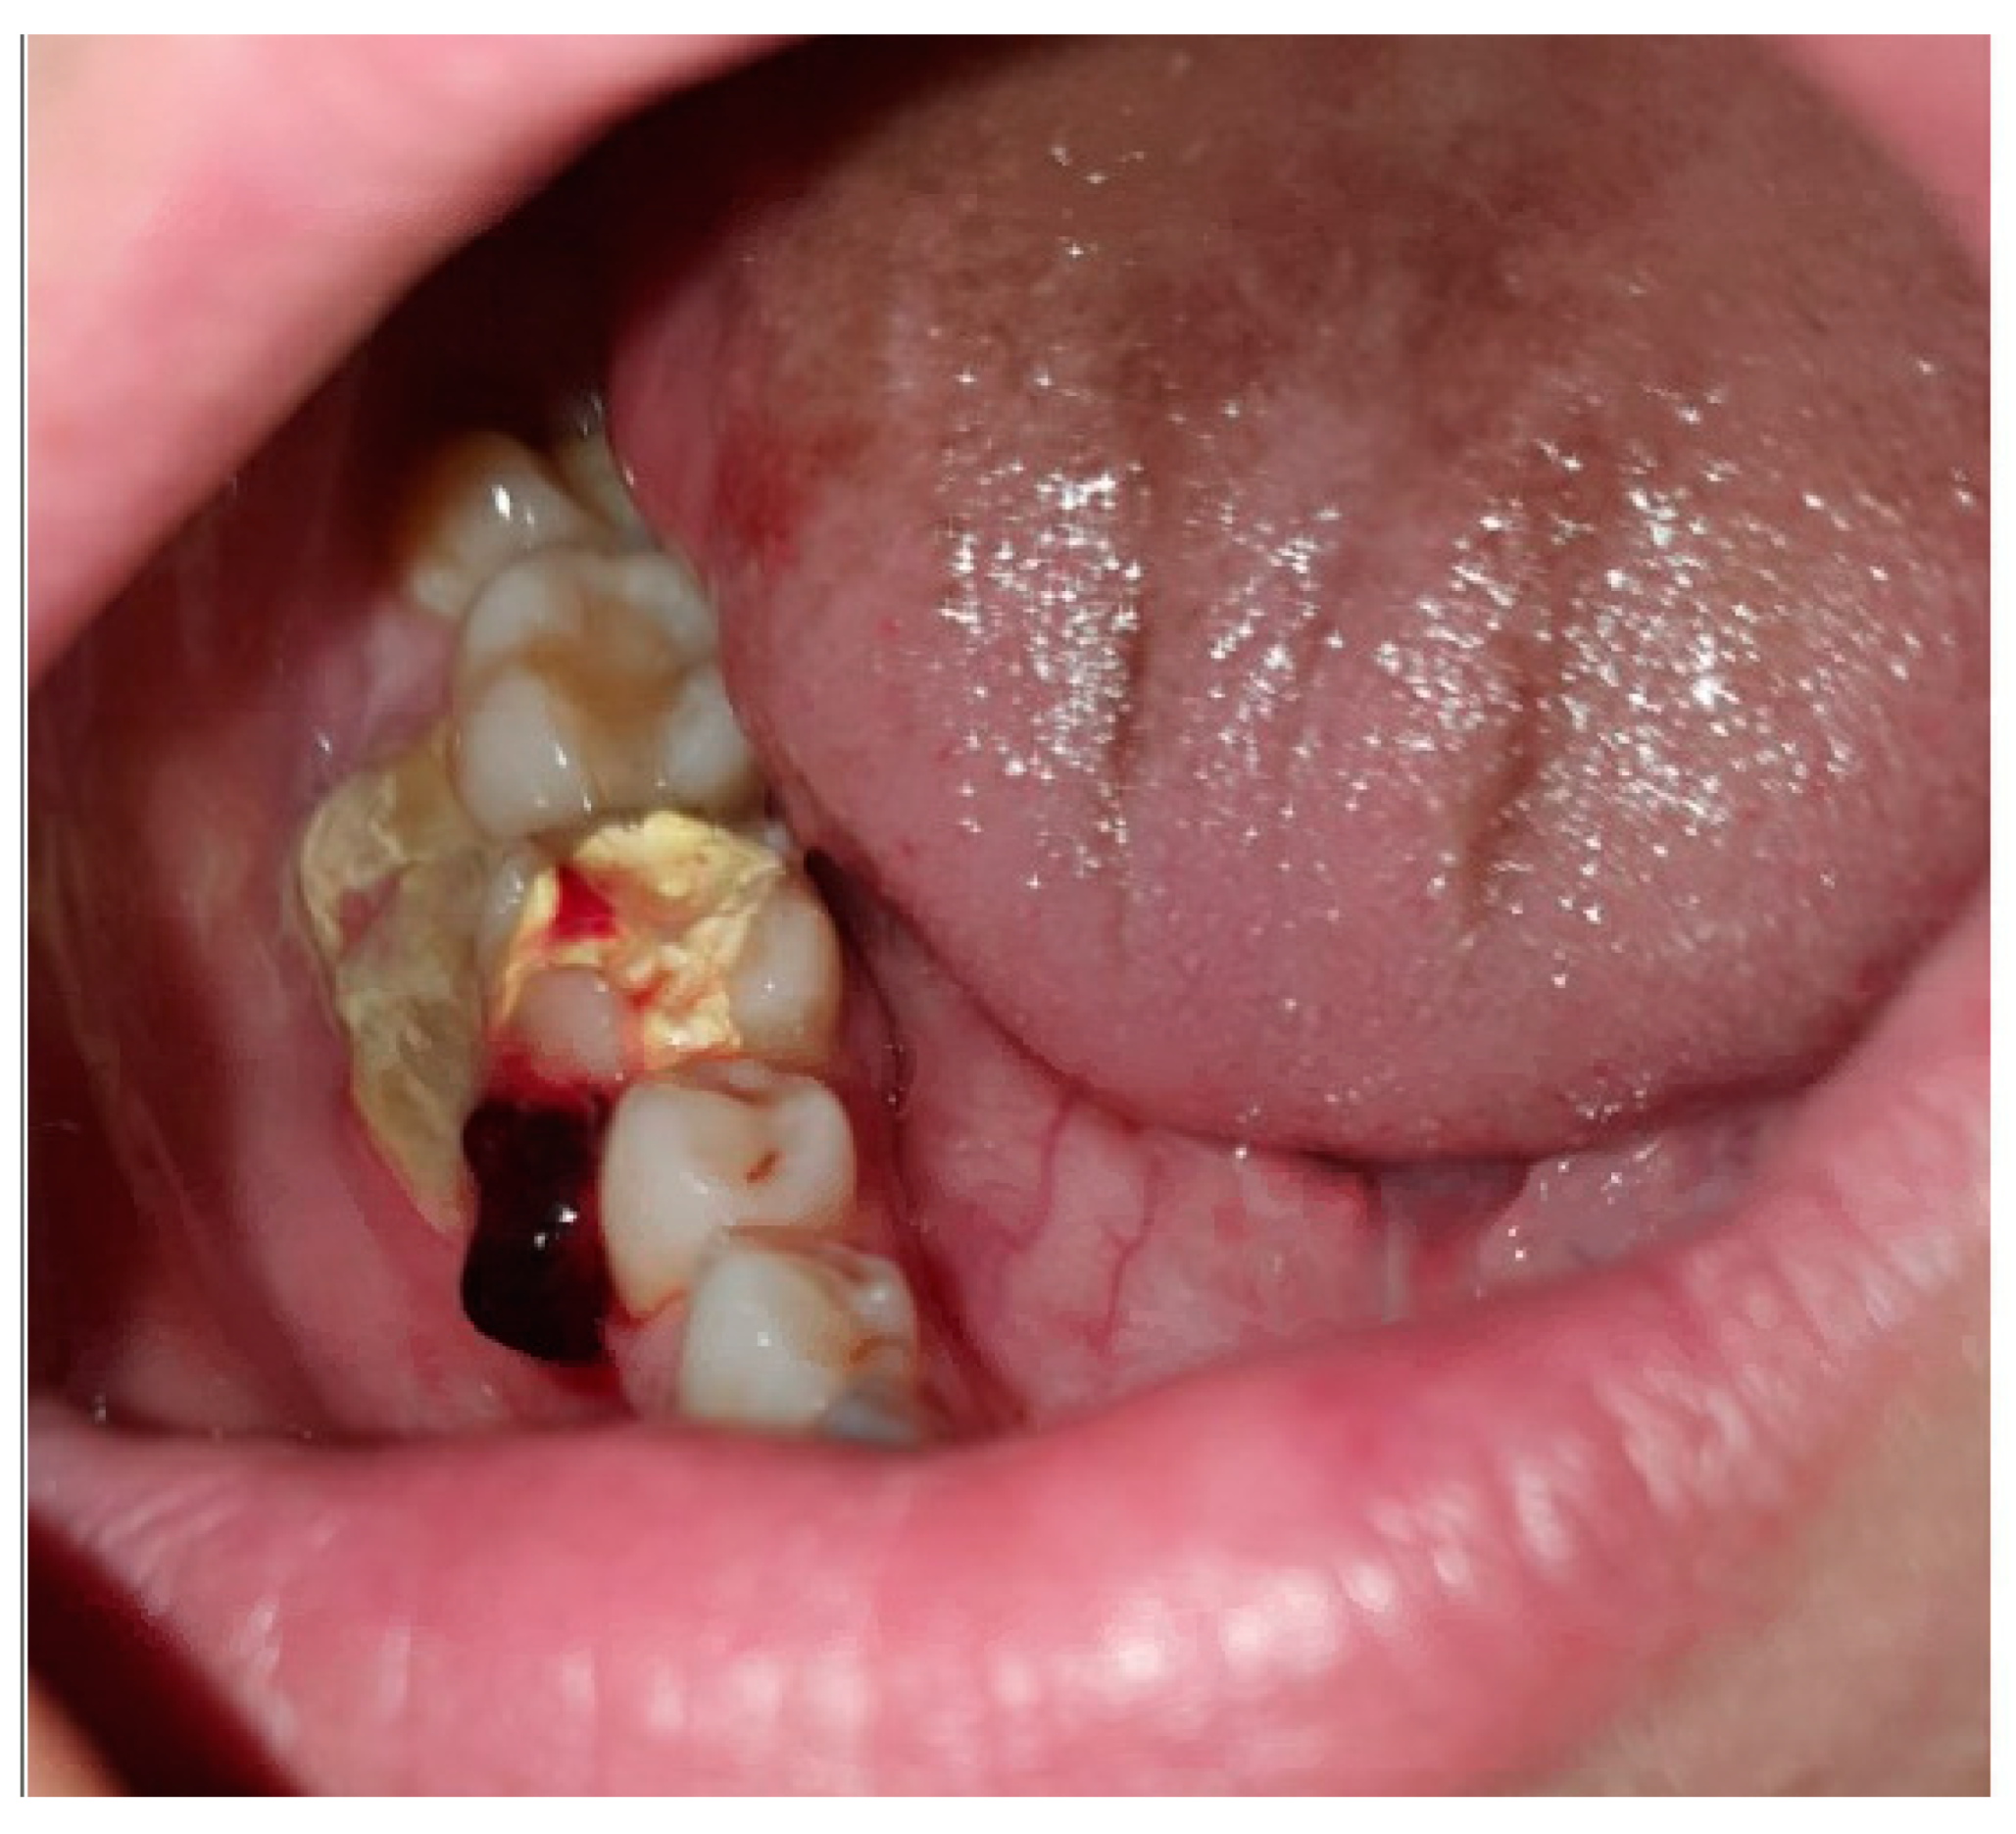

2. Case Presentation

2.1. Clinical Examination